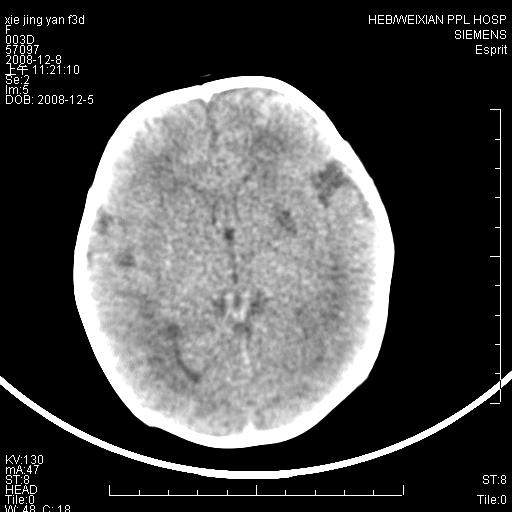

标题: PED1679:最小的“脑梗死”患者,能下其他诊断吗?

女,三天。呕吐,右侧上肢抽搐5小时。新生儿缺氧缺血性脑病有这样在基底节区出现缺血性表现的吗,并且有一侧肢体症状。

病灶局限,余脑质密度均匀,灰白质分界可.考虑脑梗死

新生儿缺血缺氧性脑病,左侧脑室旁脑白质软化

一侧肢体有症状,而且发生在灰质,边界较清晰。还是先考虑脑梗死!~!建议mri检查